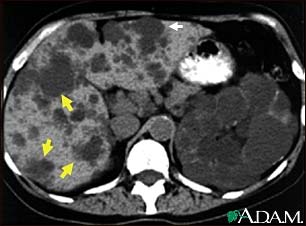

Kidney and liver cysts - CT scan

This abdominal CT scan shows cysts in the liver and kidneys (polycystic disease). The liver is the large organ on the left side of the screen. The dark spots in the liver are cysts.